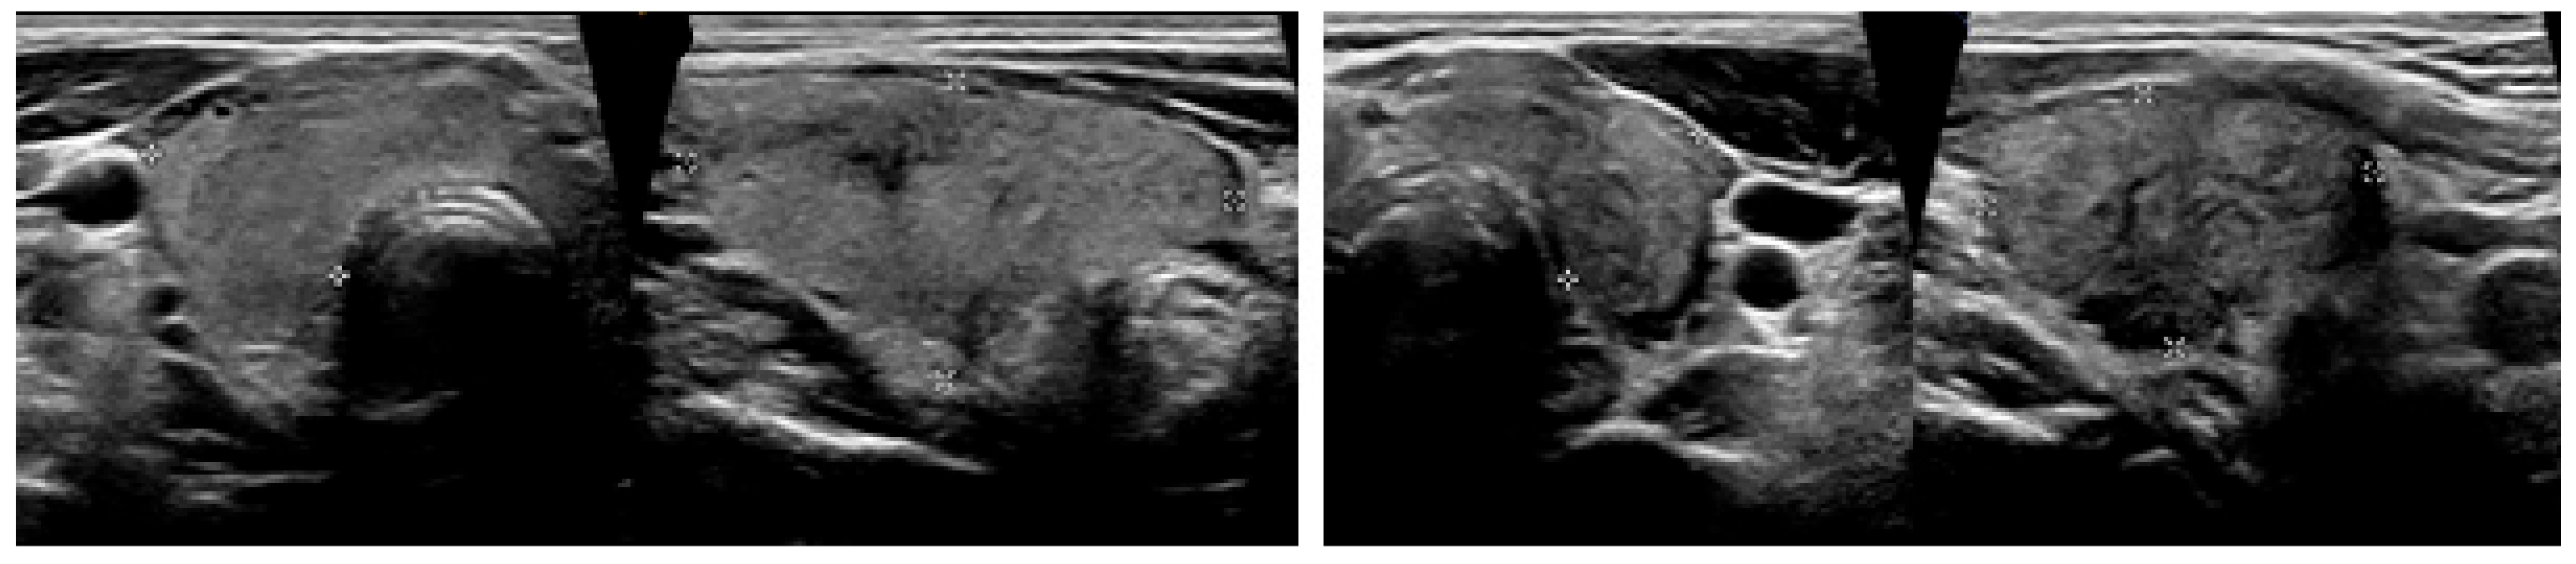

It was noted in the report that the finding could be compatible with thyroiditis and that the patient was promptly presented at our Out-Patients Department of Thyroid Diseases, where an ultrasound of the neck was performed. It showed an enlarged thyroid gland with heterogeneous echostructure. Both lobes had hypoechoic areas with ill-defined margins. There was one nodule seen in the right thyroid lobe, measuring up to 1 cm (Figure 2). Color flow Doppler showed reduced blood flow in both lobes.

Figure 2.

Ultrasound images at the time of the diagnosis of SAT. The total volume of the thyroid gland was about 18 mL (right lobe 10.1 mL and left lobe 7.2 mL) with heterogeneous echotexture and hypoechoic areas with ill-defined margins. SAT, subacute thyroiditis.